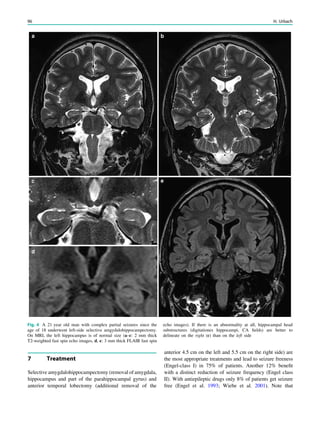

28 H. Urbach

How to Perform MRI

Horst Urbach